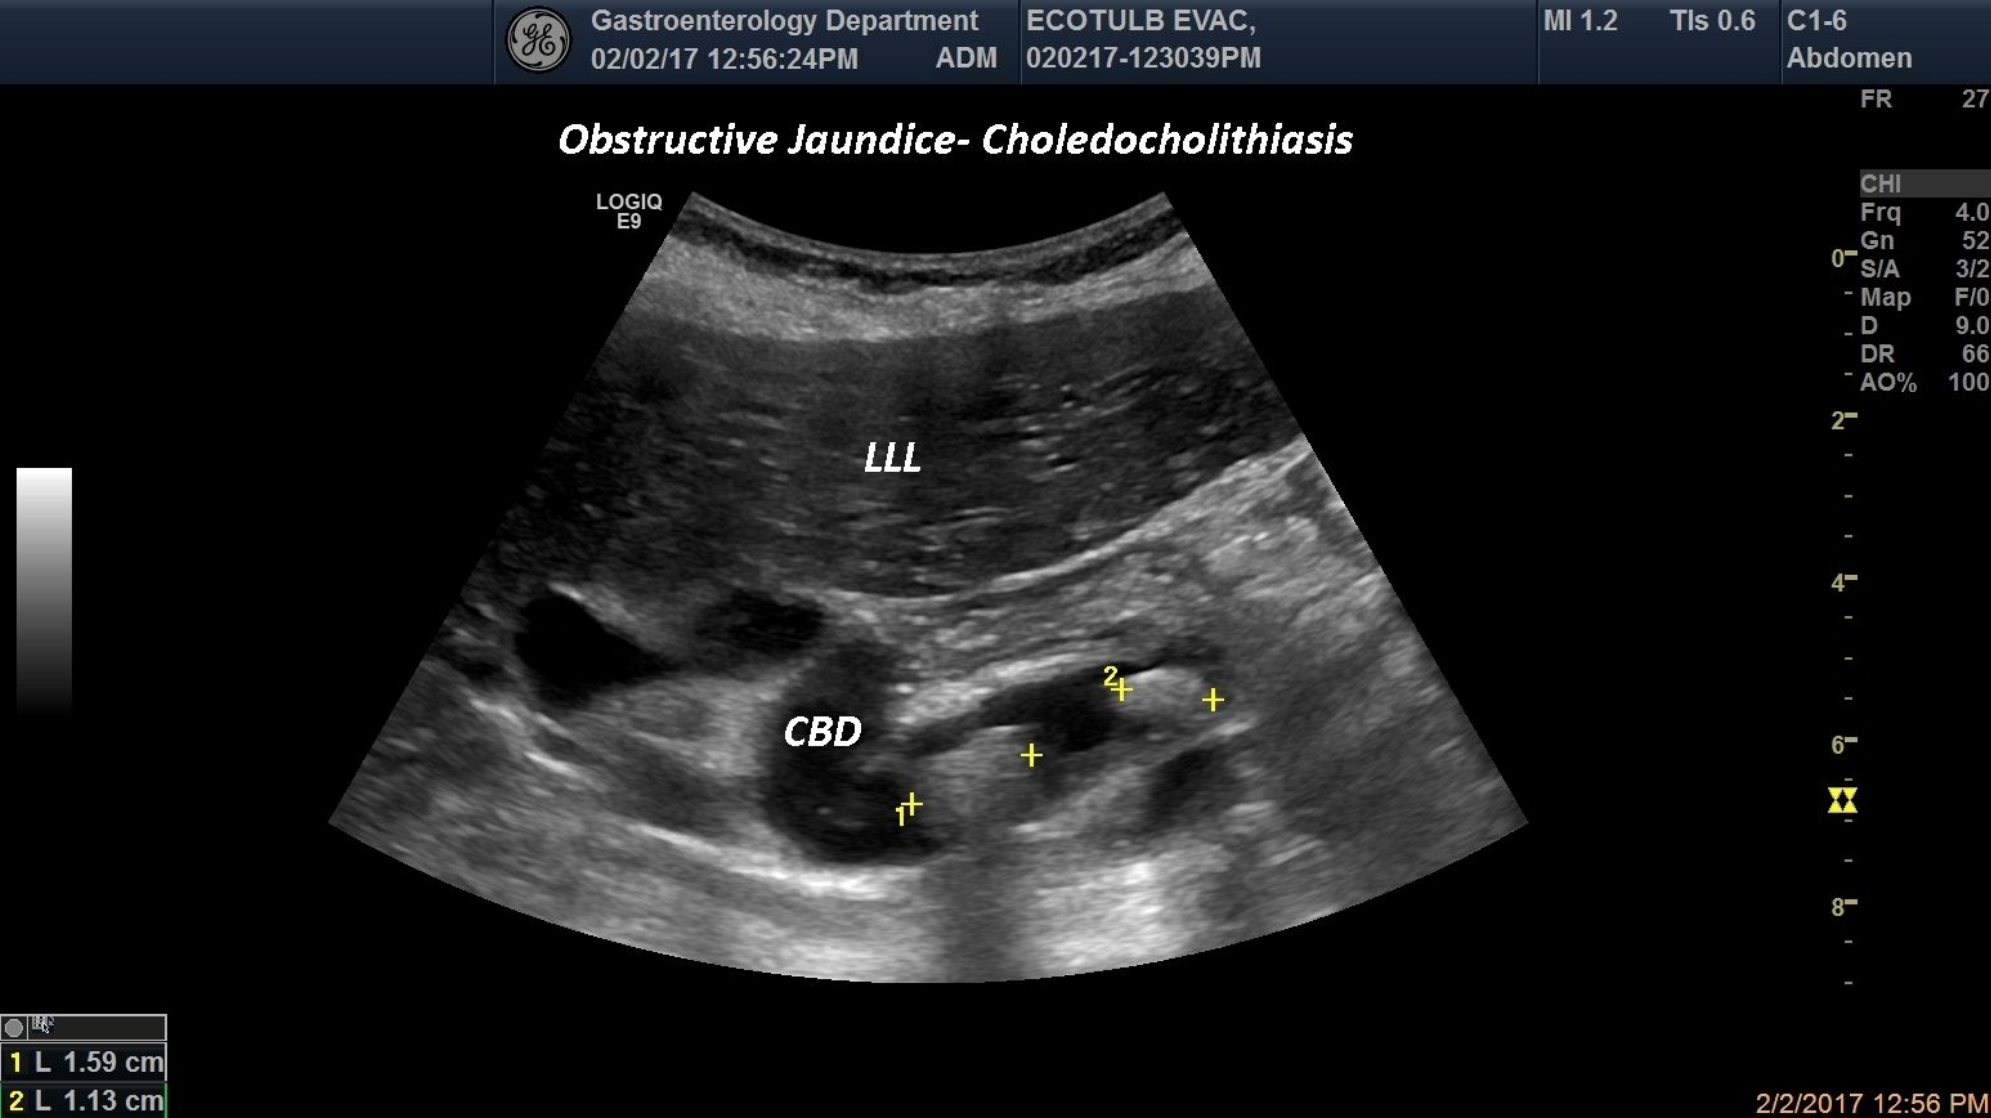

TITLE: Obstructive jaundice, Choeledocholithiasis

The image displayed shows a tortuous choledocus with at least two hyperechoic structures, with posterior shadowing representing gallstones inside the common bile duct and dilated biliary tree.

common bile duct, gallstones, obstructive jaundice